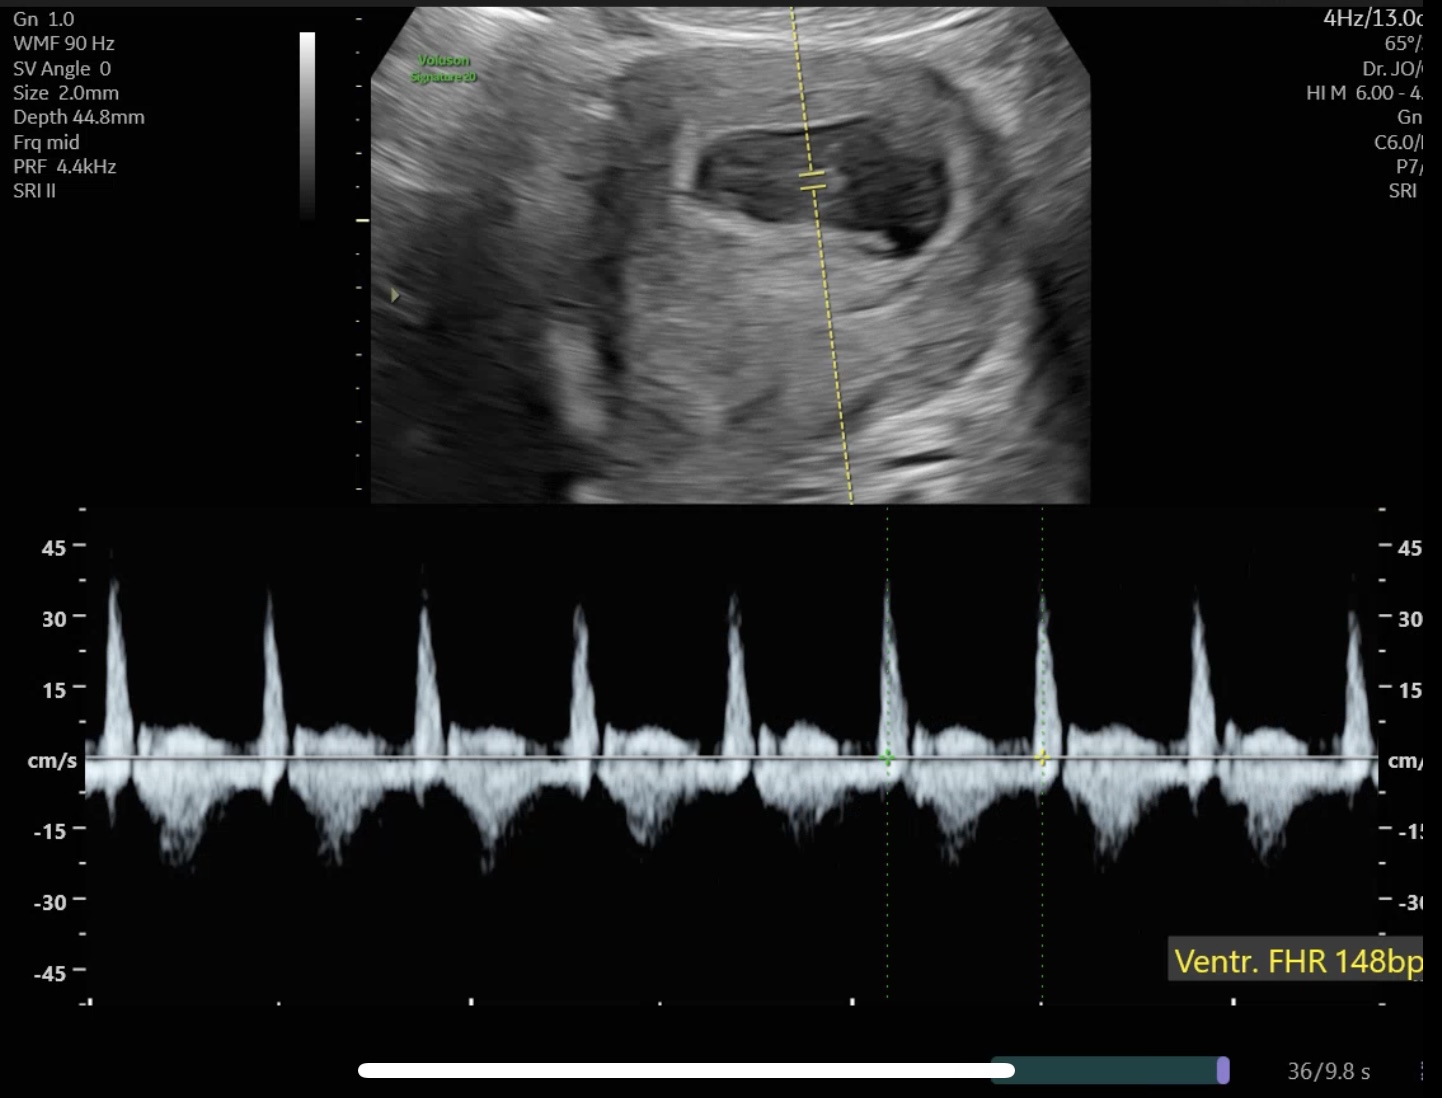

7주 2일차 산부인과 진료에서는

아기의 심장 소리를 처음 들었다.

주수에 맞게 규칙적인 박동이 확인되었고,